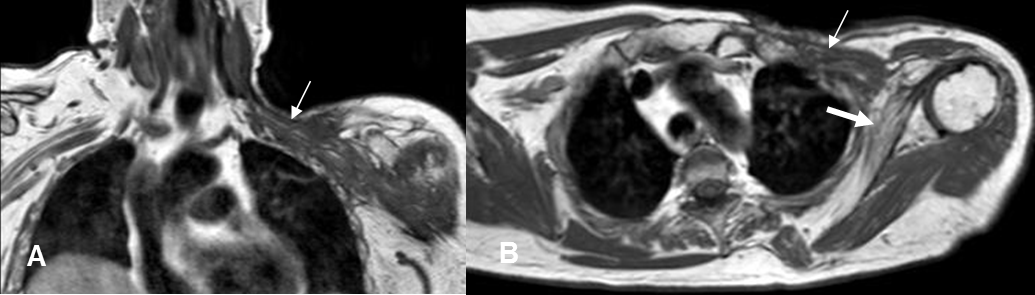

Fig 29 D. Atrofia muscular.

A: RM coronal en T1 y B: RM axial en T1. Paciente con tumor de mama metastásico supraclavicular, tratado con cirugía y radioterapia. Pérdida de la grasa y fibrosis, sobre las raíces nerviosas, (Flechas delgadas) que se asocia con atrofia del músculo subescapular, el cual es mas pequeño y con recambio graso. (Flecha gruesa).